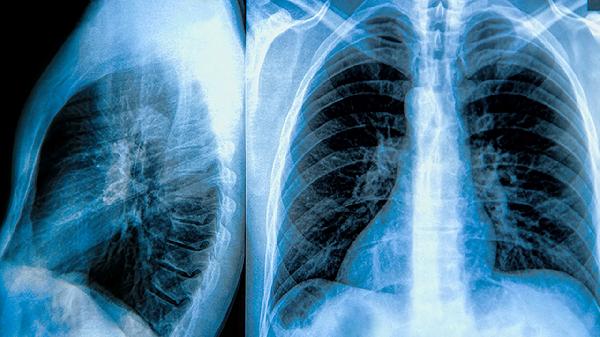

肺气肿合并肺大泡的治疗方法主要有戒烟干预、支气管扩张剂使用、糖皮质激素治疗、肺减容手术、肺移植手术。

针对巨大肺大泡压迫正常肺组织的情况,可采用胸腔镜下行肺大泡切除术。手术可改善通气/血流比例失调,术后需配合呼吸康复训练恢复肺功能。

日常需保持低盐高蛋白饮食,每日补充1.2g/kg优质蛋白质维持呼吸肌功能。推荐八段锦等温和运动改善肺活量,训练时采用缩唇呼吸法控制呼吸频率。冬季注意佩戴口罩预防呼吸道感染,定期复查胸部CT监测肺大泡变化。氧疗患者需将血氧饱和度维持在90%-92%区间,避免二氧化碳潴留加重。